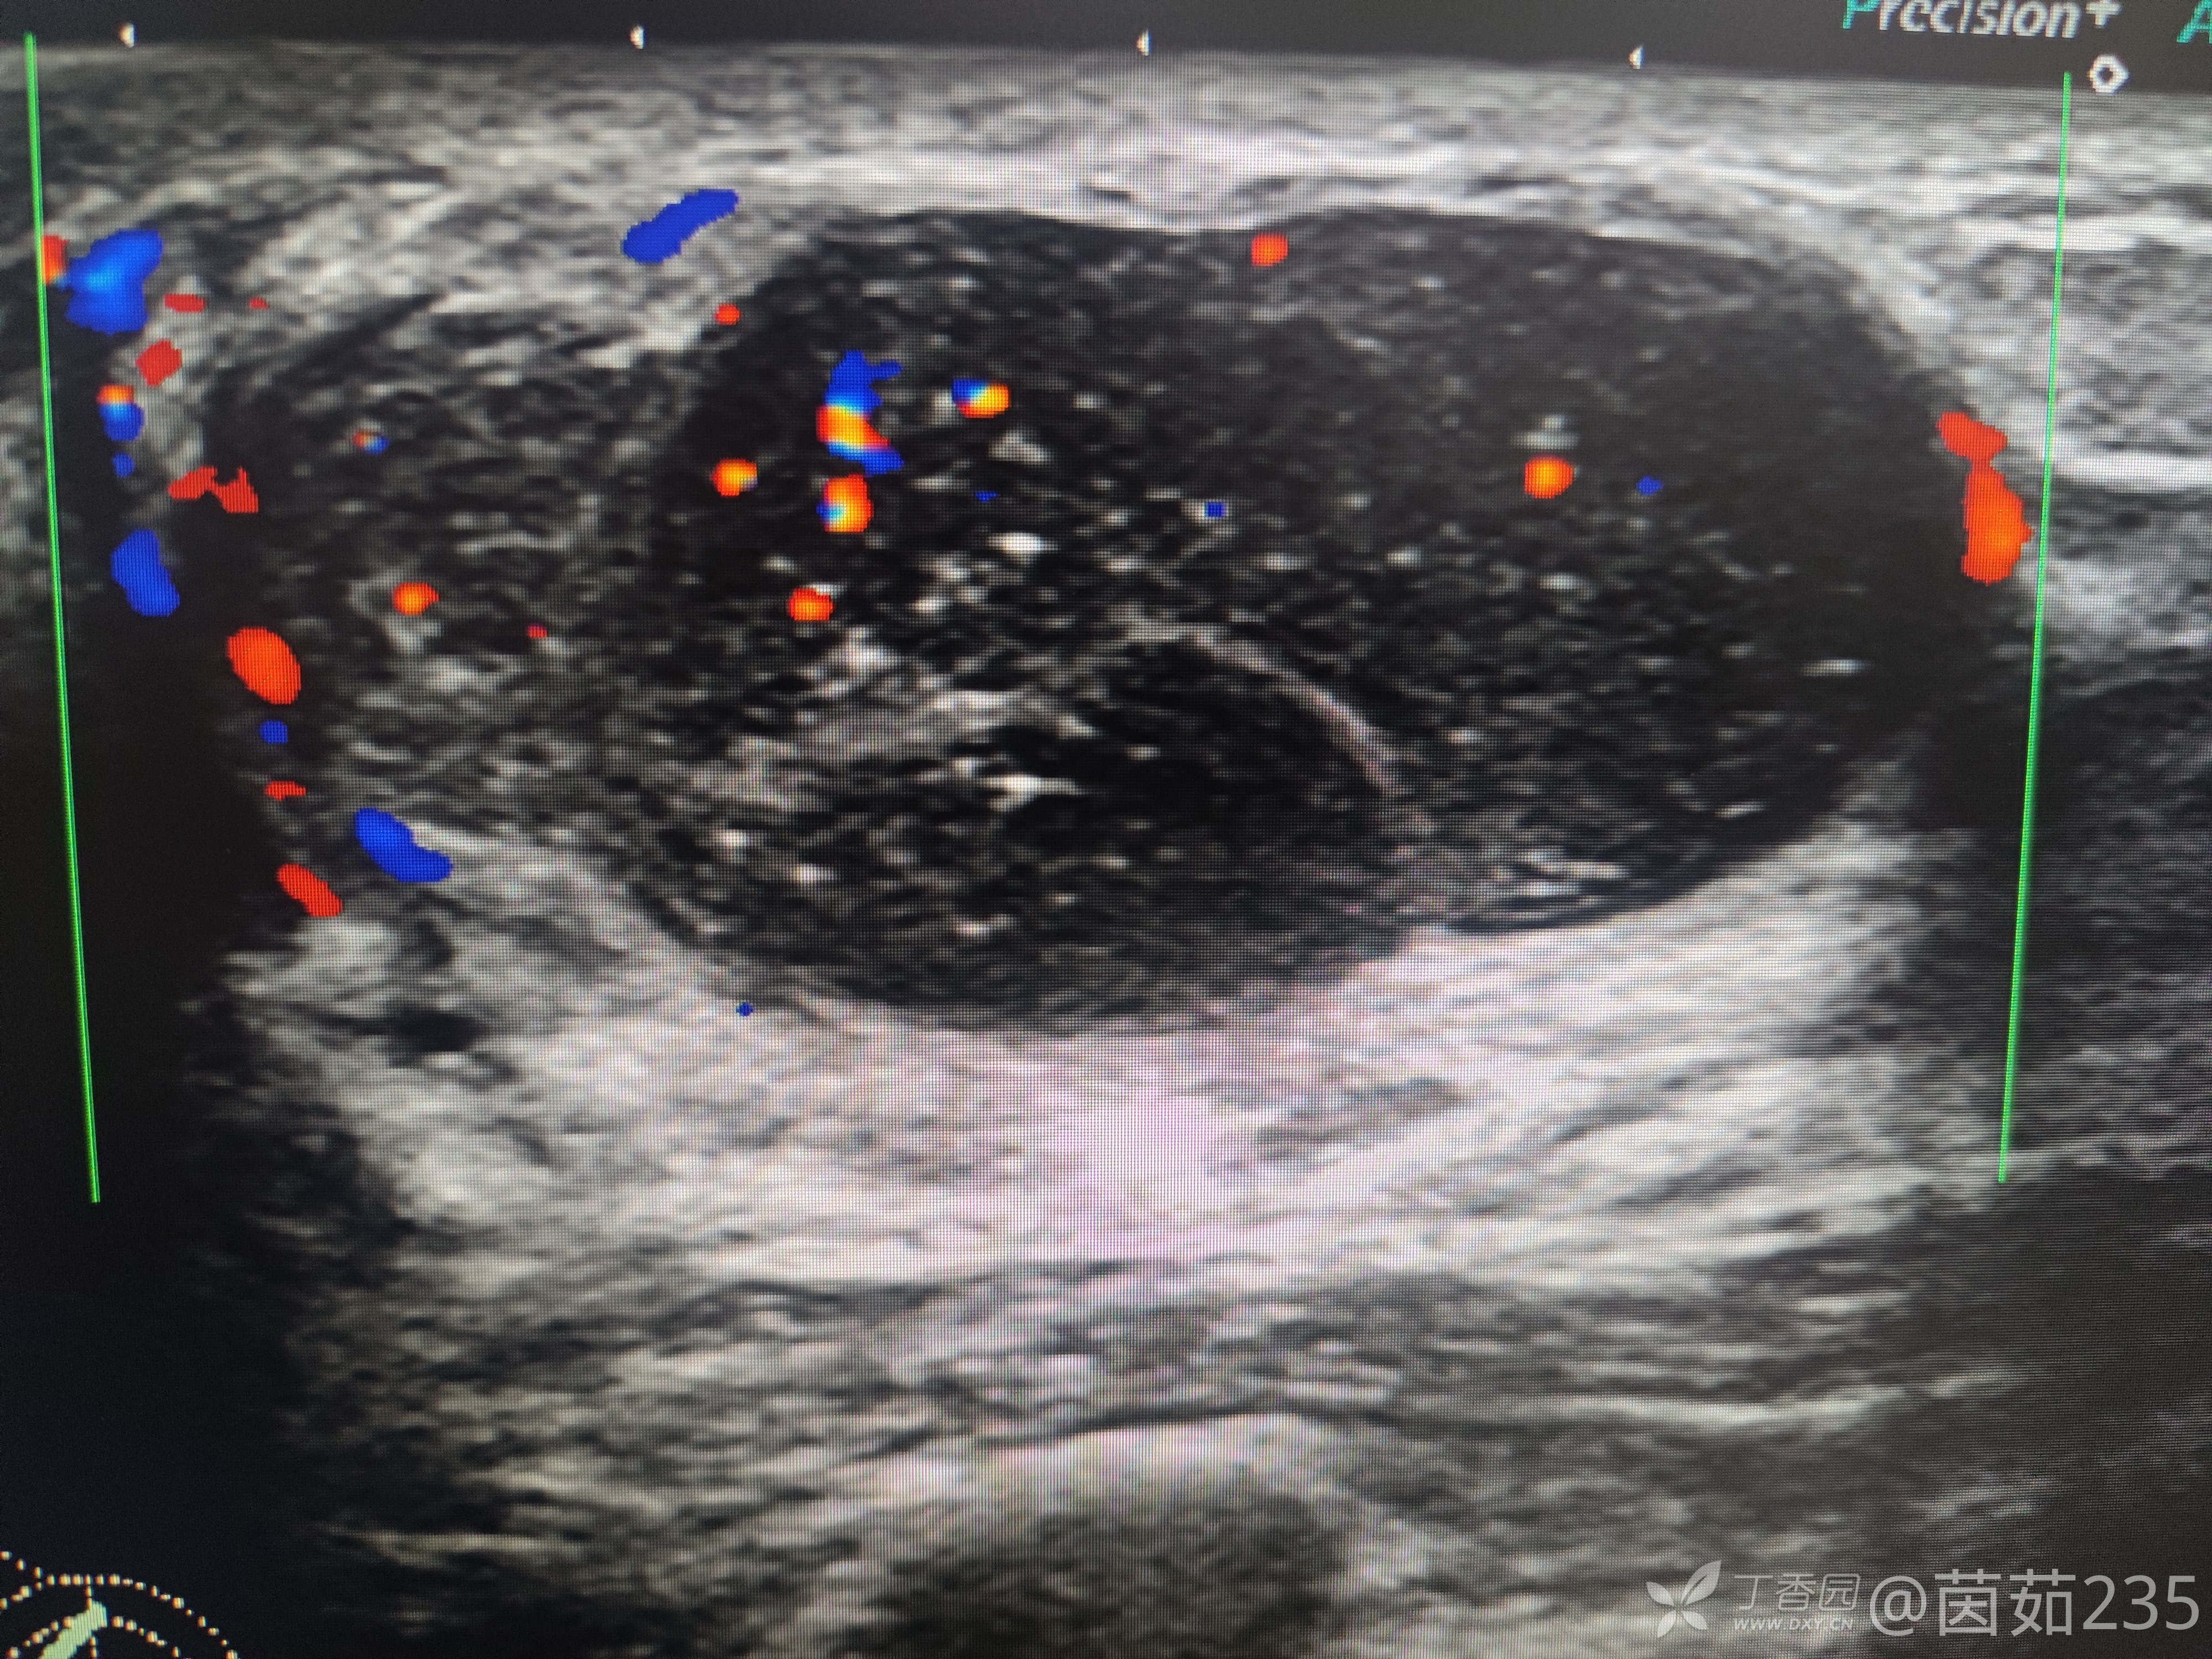

右侧乳腺12点乳晕后方腺体内可见一低回声包块,大小37✖️16mm,边界清,壁厚,内回声不均,可见数个彗星尾。来看看图,你们觉得该分几类?考虑是什么?